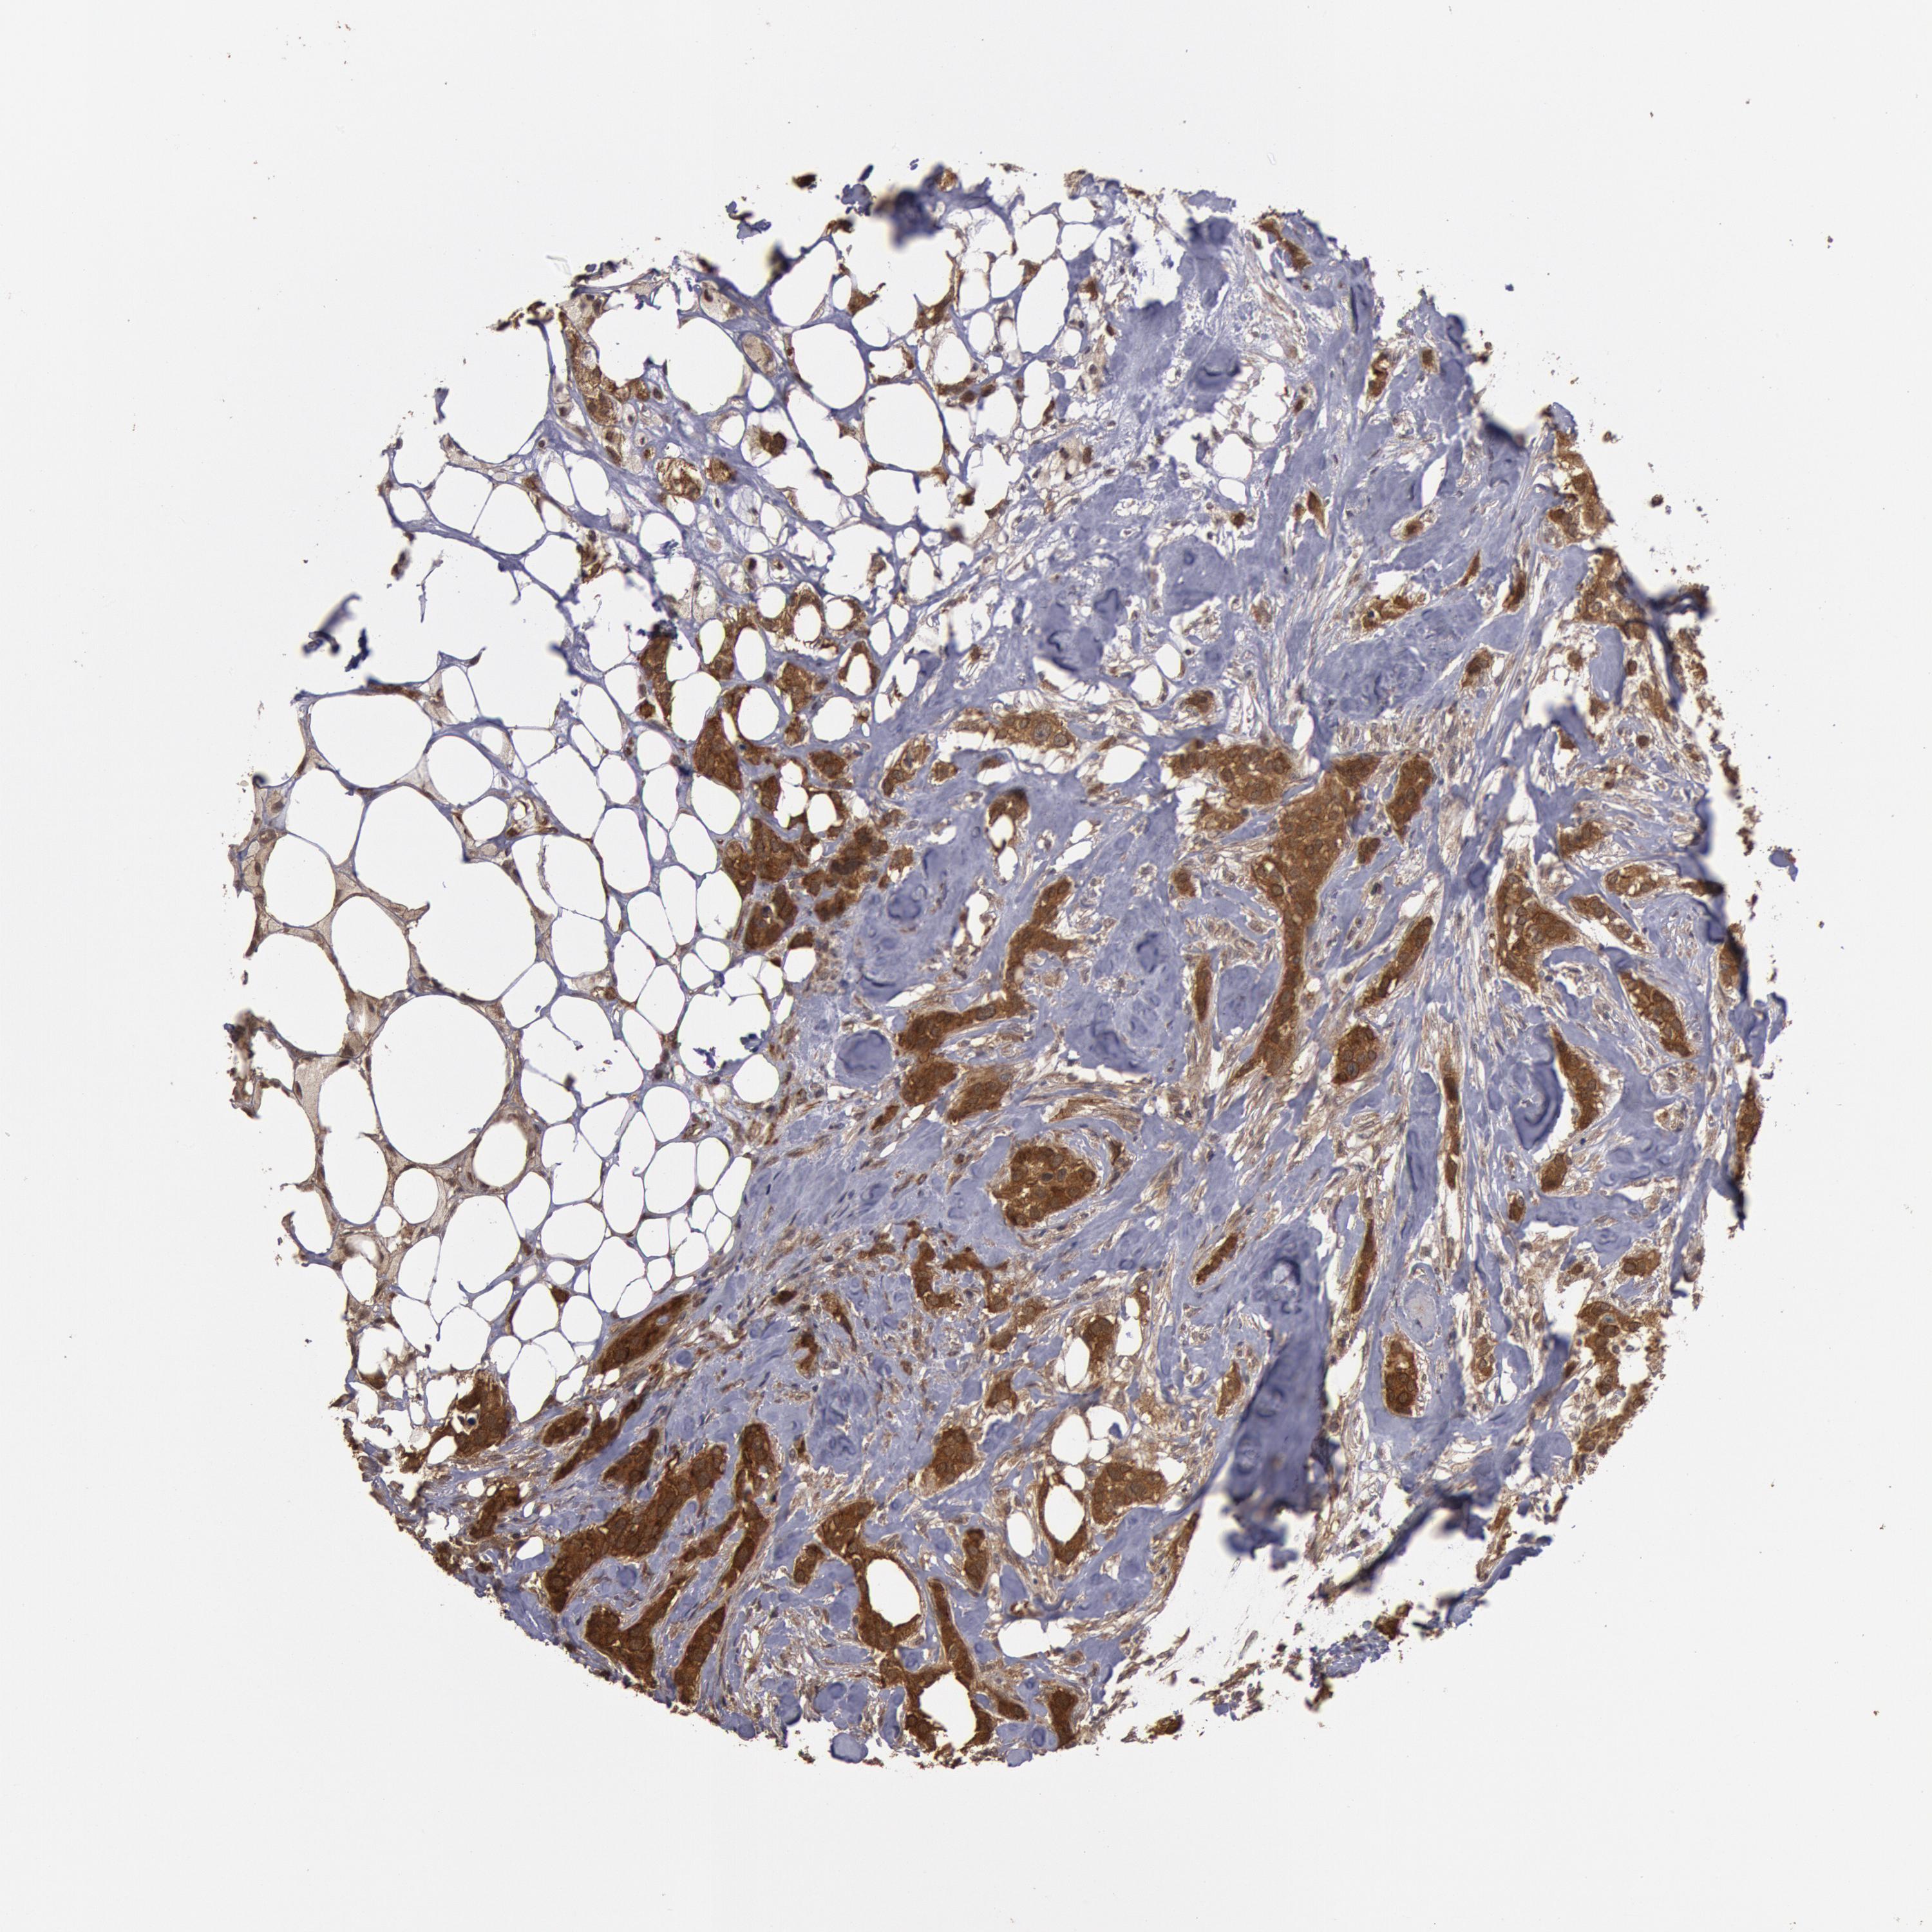

CANCER BREAST CANCER Show tissue menu

BRCA TCGA BRCA VALIDATION PROTEIN EXPRESSION

ANTIBODIES

AND

VALIDATION